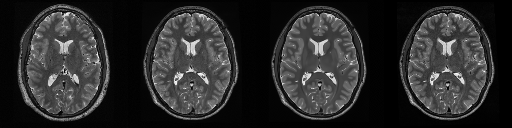

HCP T2w dataset

We utilize images from the publicly available Human Connectome Project (HCP) [51] T2-weighted (T2w) images dataset for the task of compressed sensing, which contains brain images from 47 patients. The HCP dataset includes cross-sectional images of the brain taken at different levels and angles.

Compressed sensing

We train a flow-based model from scratch on 10,000 randomly sampled images, utilizing the ncsnpp architecture [9] with minor adaptations for grayscale images. We employ compression rates , meaning . The measurement operator is given by a subsampled Fourier matrix, whose sign patterns are randomly selected. We evaluate our reconstruction algorithm’s performance on 200 randomly sampled test images.

We present the quantitative and qualitative results of compressed sensing in Tab. 1 and Fig. 4, respectively. As shown in Tab. 1, our method consistently achieves the best performance across varying compression rates . In Fig. 4, our method produces reconstructions that are more faithful to the original images, with fewer artifacts, leading to higher accuracy and clearer details.